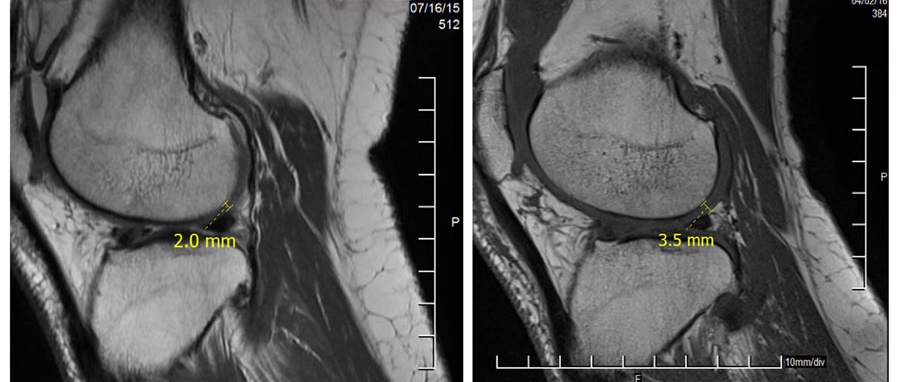

2) 무릎 MRI 검사

fig2 2

줄기세포 주사 전에 연골의 두께가 2.0mm이었는데 줄기세포 주사 후에는 3.5mm로 증가된 것을

볼 수 있습니다. 줄기세포의 연골 재생으로 무릎 연골의 두께가 증가된 것으로 판단됩니다.